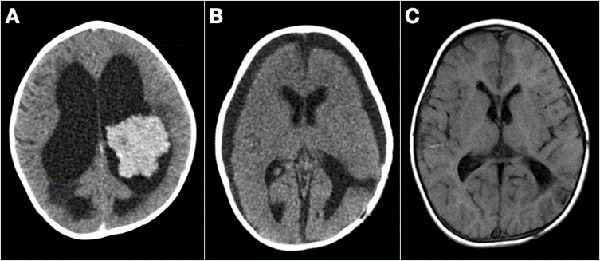

Figura 5: Tumores agresivos. A) Paciente de 8 meses de vida, sexo masculino, presentó irritabilidad, macrocefalia y somnolencia. TC de cerebro con contraste EV donde se observó imagen en región pineal que se extiende al tercer ventrículo. Se realizó cirugía de exploración, exéresis parcial, anatomía patológica informó pineoblastoma, paciente falleció a los 5 meses por progresión de la enfermedad. B) Paciente de 2 meses de vida, sexo masculino, consultó por deterioro progresivo del sensorio. TC de cerebro con contraste EV que evidenció lesión centroencefálica e hidrocefalia obstructiva. Se realizó cirugía de exploración de lesión, con colocación intraquirúrgica de drenaje ventricular al exterior. Anatomía patológica informó tumor embrionario indiferenciado. Paciente falleció a los 14 días por progresión de enfermedad. C) Paciente de 19 meses de vida, sexo femenino, consultó por vómitos a repetición. IRM de cerebro con contraste EV que mostró tumor supratentorial intraventricular con realce homogéneo con el contraste EV. Se realizó cirugía de exploración, con exéresis parcial por el intenso sangrado. Anatomía patológica informó carcinoma de plexos coroideos. Paciente fallece a los 3 meses.

Analizando por separado los resultados de anatomías patológicas vemos que los ATRT, meduloblastomas y ependimomas tuvieron una supervivencia del 32% a los 5 años (Figuras 3 y 4) y los pacientes con tumores embrionarios, PNET, carcinomas y papilomas atípicos de plexos coroideos y pineoblastomas presentaron una mortalidad del 100% a los 5 años (Figuras 5 y 6). Por otro lado, los papilomas de plexos coroideos, lesiones más frecuentes en el grupo 1, tuvieron un 100% de supervivencia a los 10 años, al igual que los astrocitomas y gliomas de bajo grado (Figuras 7 y 8).

Figura 7: A) Paciente de 13 meses, sexo masculino, consultó por alteraciones en la motricidad. TC de cerebro con contraste EV que evidenció lesión intraventricular que realza homogéneamente e hidrocefalia, se colocó DVE previo a cirugía de exéresis tumoral. B) TC de cerebro luego de cirugía, diagnóstico de papiloma de plexos coroideos, se retiró el DVE a las 48 hs. TC de cerebro de control al año con colecciones subdurales crónicas. Se decidió conducta expectante de las mismas. C) IRM de cerebro control a los 3 años, sistema ventricular de tamaño normal, corticotomía cerrada. Paciente sin secuelas neurológicas.

Figura 8: A y B) Paciente de 21 meses de vida, sexo femenino, que presentó hemiparesia faciobraquiocrural derecha, vómitos y deterioro del sensorio, TC de cerebro con contraste EV, lesión supra e infratentorial, con gran efecto de masa con compresión del tronco del encéfalo. Se realizó cirugía de exploración y exéresis parcial. Anatomía patológica informó papiloma de plexos coroideos. C y D) IRM de cerebro con contraste EV que evidenció resto tumoral intraventricular y en relación a cisternas peri mesencefálicas. Se realizó re exploración del tumor. E y F) Imagen por TC de cerebro con contraste EV postquirúrgica inmediata que evidenció exéresis total.